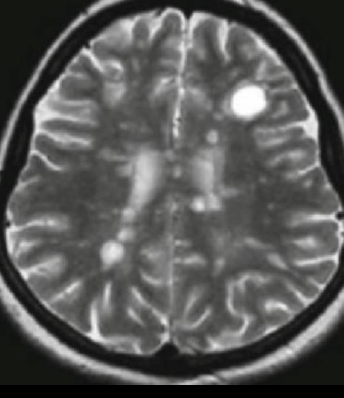

A

T2

Dedos de dawson

activa